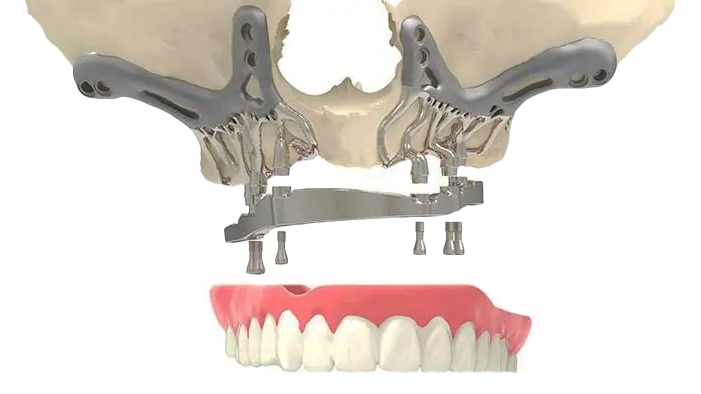

Zygomatic implants and subperiosteal implants are both solutions for patients with insufficient bone in the upper jaw, but they differ significantly in design and placement. Zygomatic implants are long implants anchored into the zygoma, or cheekbone, providing a robust foundation for dental prosthetics, especially in cases of severe maxillary atrophy. They are placed through the alveolar crest and reach into the dense zygomatic bone, offering immediate stability and support.

Subperiosteal implants, on the other hand, are custom-made frames that sit on top of the jawbone but underneath the gum tissue. These implants do not anchor into the bone but rather rest on the bone surface, supported by the overlying gum tissue. This makes them suitable for patients who lack sufficient bone mass even for zygomatic implants.

The primary difference lies in the placement: zygomatic implants integrate with the bone for stability, whereas subperiosteal implants rely on a framework resting on the bone surface, making them a less invasive option but generally less stable over the long term.

The situational uses of zygomatic and subperiosteal implants are dictated by the extent of bone loss and the specific anatomical conditions of the patient. Zygomatic implants are predominantly used in cases of severe maxillary atrophy where traditional implants are not feasible. By anchoring into the zygomatic bone, they provide a stable foundation for dental prosthetics, making them ideal for full-mouth rehabilitation in patients with significant upper jawbone deficiency.

Subperiosteal implants, in contrast, are suitable for patients who lack sufficient bone mass even for zygomatic implants. These implants are custom-made to fit the contour of the jawbone and sit on top of the bone but beneath the gum tissue. They are often used when bone grafting is not an option or when patients prefer a less invasive procedure.

Understanding the appropriate situational uses for each type of implant ensures a tailored approach to dental restoration, optimizing outcomes based on individual patient needs and anatomical constraints.